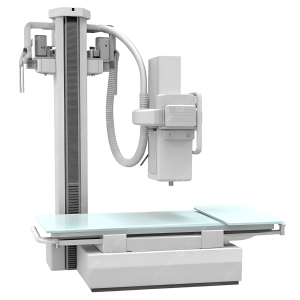

Digital Radiography